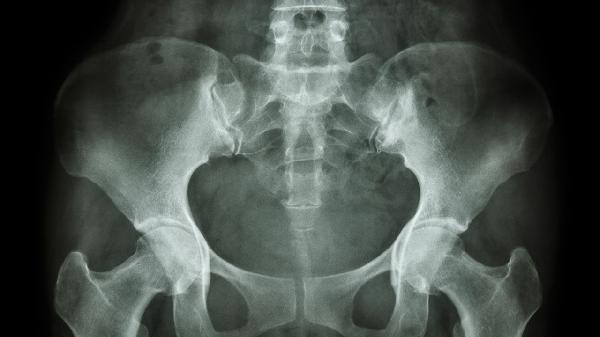

宫体朝向耻骨是指子宫体部向前倾斜贴近耻骨联合的生理位置,属于子宫前倾前屈位的正常表现之一。子宫位置受韧带、盆底肌肉及周围器官影响,多数女性为前倾位,少数为后倾位或中立位。

子宫前倾前屈位是女性生殖系统的常见解剖形态,宫体与宫颈形成约120度夹角,宫底朝向腹壁,宫体紧贴膀胱后壁。这种位置有助于维持盆腔器官稳定性,在妊娠期随胎儿增长逐渐变为直立位。前倾位通常不会引起不适,部分女性可能因体位改变出现轻微下腹坠胀感,但多数无需特殊处理。日常适度核心肌群锻炼如凯格尔运动可增强盆底支撑力。

若伴随持续下腹痛、性交痛或月经异常,需排查子宫腺肌症、盆腔炎等病理因素。超声检查可明确子宫位置及是否存在粘连,妇科双合诊能评估子宫活动度。后倾位子宫可能增加经血排出阻力,但仅少数会引发痛经或受孕困难,必要时可通过手法复位或悬吊术矫正。